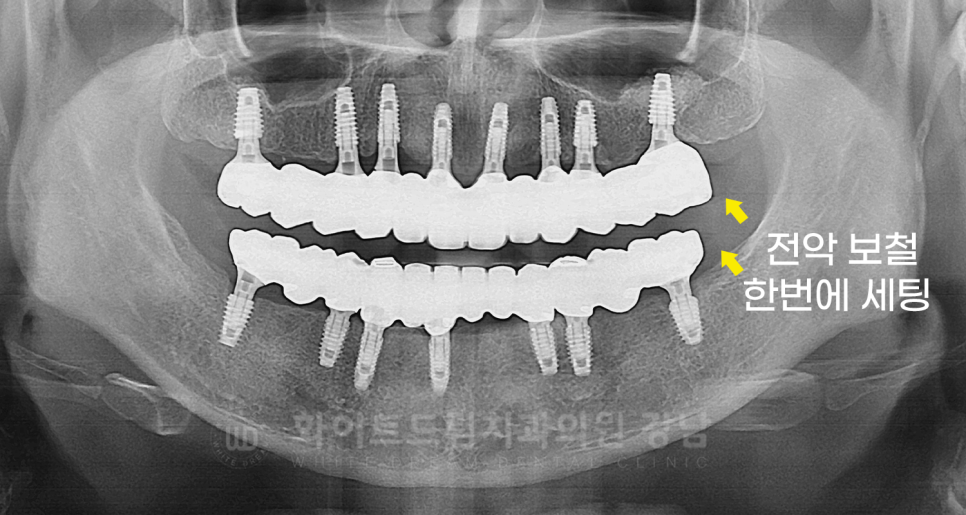

환자분의 최종 크라운 세팅 후 X-RAY 사진입니다.

환자분처럼 전체 임플란트, 전악 보철 세팅은 교합 확인을 위해

모든 크라운을 당일 세팅하게 됩니다.

치아가 상실되어 교합이 무너진 부분을 다시 복구해야 하기에

나누어서 진행하면 교합을 맞추기가 힘들기 때문이죠.